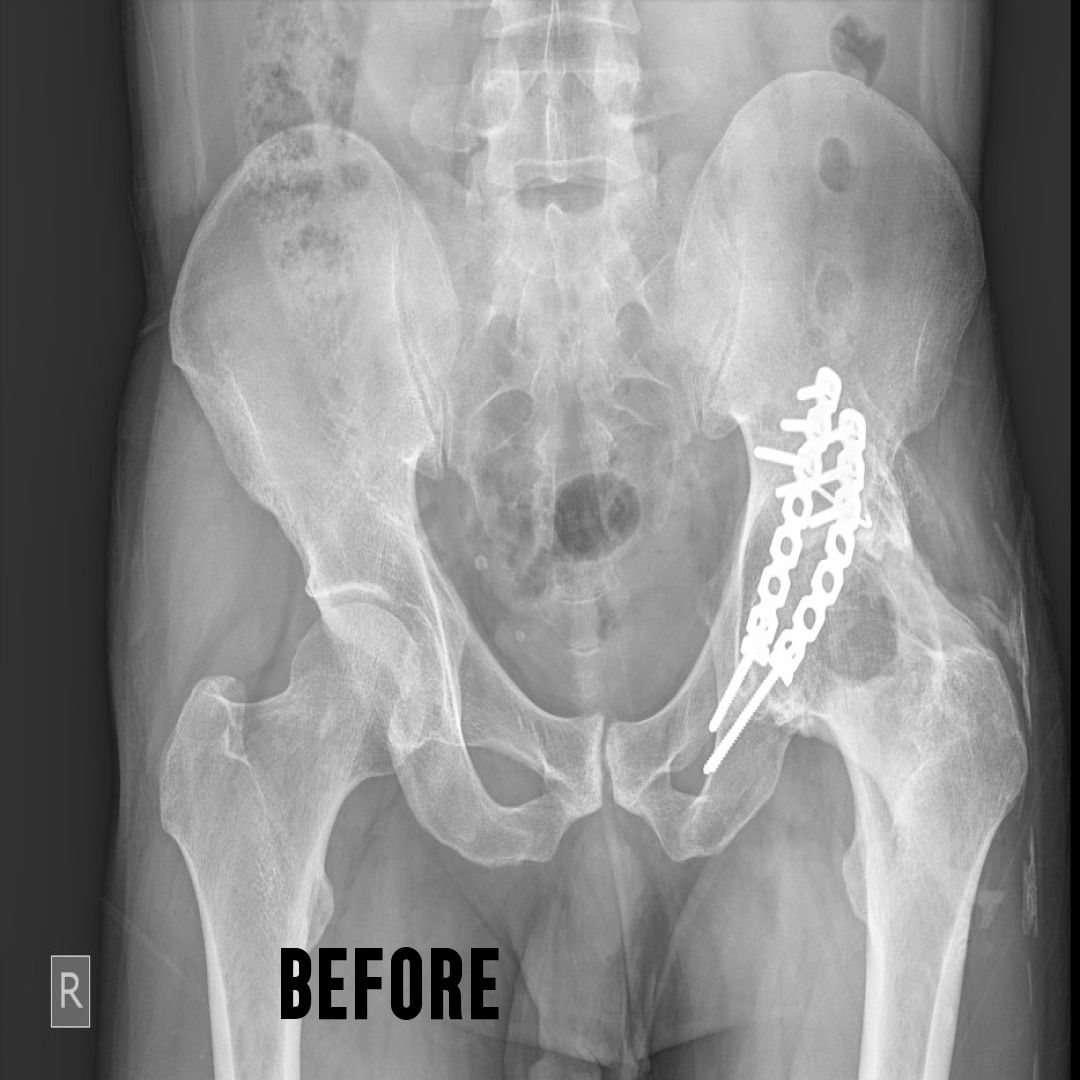

This is a surgery where both the ball and socket of the hip joint are replaced with artificial materials.

The normal hip joint consists of a cup called the acetabulum into which articulates a head of the thigh bone called the femur.

This joint may become damaged due to a variety of conditions. The common

causes are rheumatoid arthritis, ankylosing spondylitis, childhood diseases

like perches, injury to the hip joint etc. There is loss of articular cartilage, a

smooth lining of the ends of the bone in a joint. The result is that raw bones rub against each other causing pain. This condition where the articular

cartilage is damaged, is collectively called arthritis.

Damage to hip joint can occur at any age. Total hip replacement can be done

after the age of 20 years...Learn More